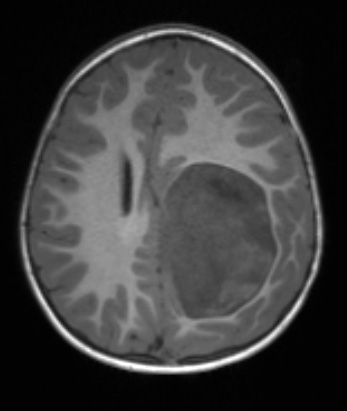

Case 8 History ---- The patient is a 2-year-old boy presenting with right-sided dysmetria & ataxia. Imaging shows a heterogeneously enhancing left parietal mass with calcifications and hemorrhage. Operative procedure: Left craniotomy for tumor resection. ---- 8A1-4 MRI Studies 8A1,2 The mass is hypointense without (8A1) and with (8A2) contrast in this T1-weighted image.